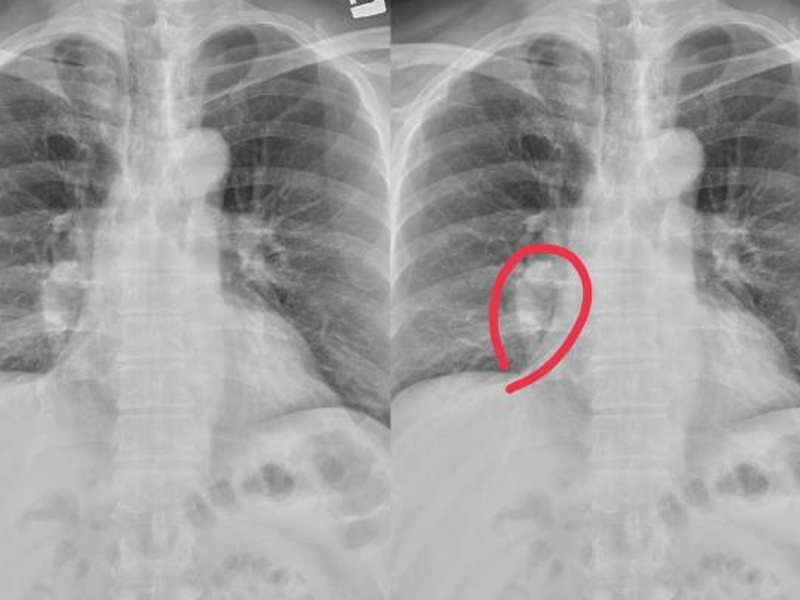

| 近日,中國江蘇省杭州市一名 50 歲的李姓婦女因雙腿莫名發癢兩個月而求醫,最終確診為原發性肝癌。起初,她以為是皮膚過敏,但服用抗過敏藥物後症狀並未改善,隨後連上半身也開始出現類似情況。最終,在衛生服務中心醫師的建議下進行腹部彩超檢查,發現肝臟異常,轉診至浙大二院進一步檢查後確診為肝癌。幸運的是,由於發現得相對及時,經過手術切除腫瘤,李女士正在逐步康復中。 身體發癢與肝癌的關聯 全科副主任醫師指出,肝臟是一個「悶葫蘆」器官,內部沒有痛覺神經,因此即便肝細胞損傷嚴重,患者也可能不會感到明顯不適。這使得肝癌在早期特別難以察覺,許多患者一發現病情即已進入晚期。李女士所經歷的皮膚瘙癢便是肝癌發出的一個警示信號,這種頑固性瘙癢是由於肝臟損傷激活了皮膚中的神經纖維,通過信號傳導至腦感覺皮層所致。 需警惕的四種皮膚異常 專家提醒,若皮膚出現以下四種異常情況,應當警惕可能是肝臟病變的徵兆: 皮膚瘙癢:肝臟損傷可能激活皮膚中的神經纖維,導致頑固性瘙癢。 皮膚發黃:肝功能受損會使體內膽紅素積聚,造成皮膚和眼白呈現蠟黃色。 蜘蛛痣:這是皮膚表面出現的小血管瘤,按壓時消失,放開後再次出現,通常與雌激素濃度升高有關。 出血:肝臟合成凝血因子的能力下降可引起牙齦出血、皮膚出血點或消化道出血等現象。 結語:健康不容忽視,定期檢查保平安 專家強調,對於這些看似普通的症狀,我們絕不能掉以輕心。一旦發現上述異常情況,應及時就醫進行詳細檢查,以便早發現、早治療,提高治愈率和生存質量。同時,保持良好的生活習慣和定期的健康檢查也是預防疾病的重要手段。 |